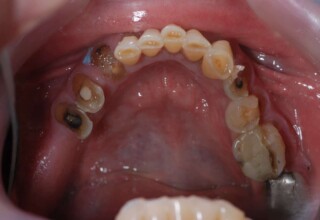

Lower jaw: extractions, direct implant placement and immediate loading (same day) with a transitional bridge.

Upper jaw: Sequential extractions, sequential implant placement and gradual incorporation in the temporary bridge so that the patient was never left without fixed teeth. The aim of the above approach was to have the patient in continuous functional and aesthetic reconstruction, without immediate loading due to anatomical restrictions. Old smiling photos of the patient were used because the natural shape of the teeth was completely lost due to repetitive prosthetic attempts. Tooth relationship and teeth-lip support was transferred to the temporary restorations. Two different transitional bridges were needed to fully estimate phonetics, mastication and esthetics. After the necessary adjustments were finalized, the temporary bridge was used as a guide for the permanent bridges.

Initial

Intermediate

Final